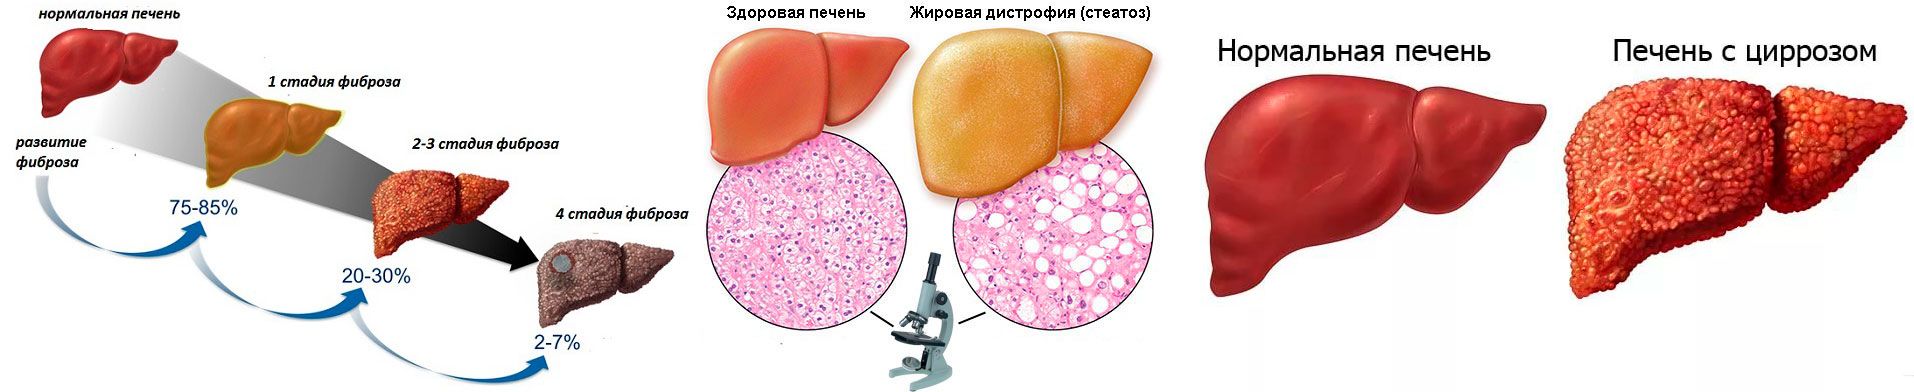

Изображения заболеваний печени: признаки и симптомы